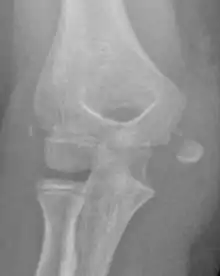

The diagnosis is confirmed with X-rays and occasionally with a CT scan.

In all injuries to the medial epicondyle, radiographs (x-rays) are imperative. Computed tomography scans are occasionally useful in evaluating the degree of fracture displacement or the involvement of the joint surface.

Displaced Fracture

Studies generally use the x-ray appearance of the arm to determine how displaced a fracture is. The definition of ‘displaced fractures' are variable, with anything from 2mm to more than 15mm;[4] however x-rays on which this assessment is made are known to be hugely misleading with fractures showing little displacement having >10mm displacement using CT scans.[5][6] The practical approach is therefore to assume that any fracture that has any degree of displacement on x-rays is ‘displaced’.